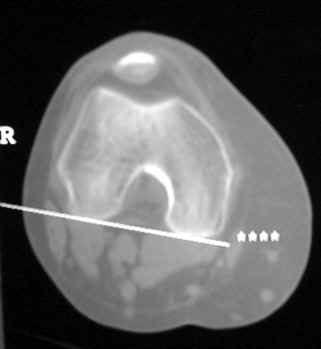

CT—Bone graft placed for patient with congenital hip dysplasia and poorly developed acetabulum (Shelf procedure). Persistent cleft between graft and native bone is present years after surgery, consistent failure of graft incorporation